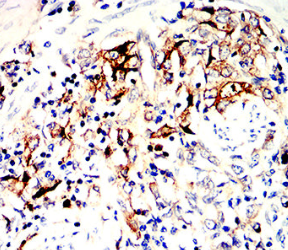

HLA-DRB1 Mouse Monoclonal antibody[5B3D2]

IHC    1/200 - 1/1000